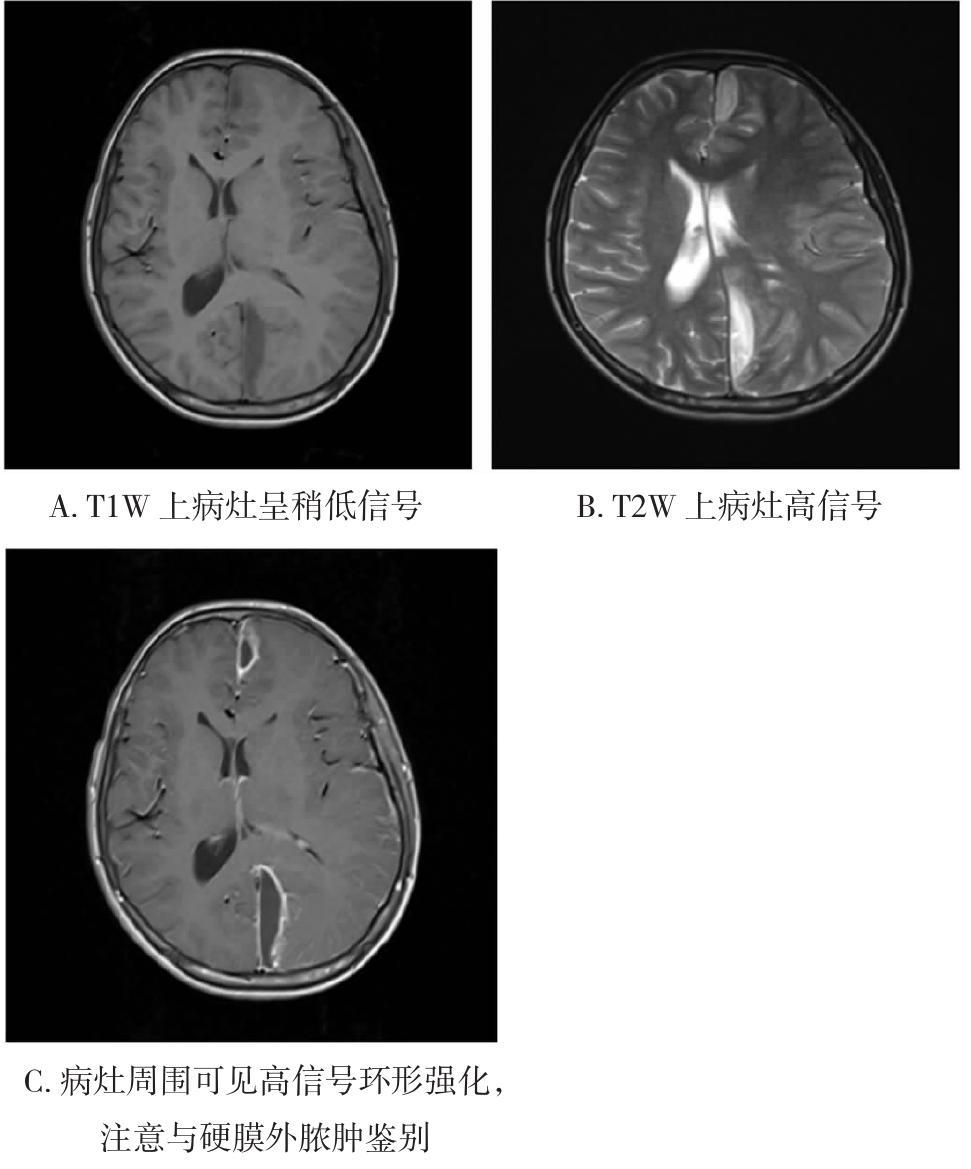

摘要:随着抗生素的广泛应用和不断更新,感染性疾病对人类健康的威胁已经得到卓有成效的控制。在二代测序、药敏试验等辅助检查手段的支持下,临床医生在多数情况下可以精确地找到责任病原体并拟定相应的治疗方案。中枢神经系统由于其特殊的解剖生理特点,一直是危重或难治性感染的好发部位。其中好发于硬脑膜及其周围结构的围脑膜感染,因其特殊的病因学及病理生理机制,成为诸多中枢神经系统感染性疾病中与外周感染联系最为紧密的一类。虽然围脑膜感染多有较典型的前驱感染,但由于其起病隐匿、症状缺乏特异性,容易被前驱感染的表现所掩盖。而一旦进入显症期则意味着中枢神经系统损害可能已经产生,且单纯的药物治疗往往无法有效控制感染。因此,临床医生早期识别和诊断围脑膜感染并及时给予相应的抗菌治疗是当下避免该类可治性神经系统疾病造成不良预后的重要方式,同时也可减少不必要的外科干预对机体的损害。

• 0+1

• 1+1

• 2+1

• 3+1